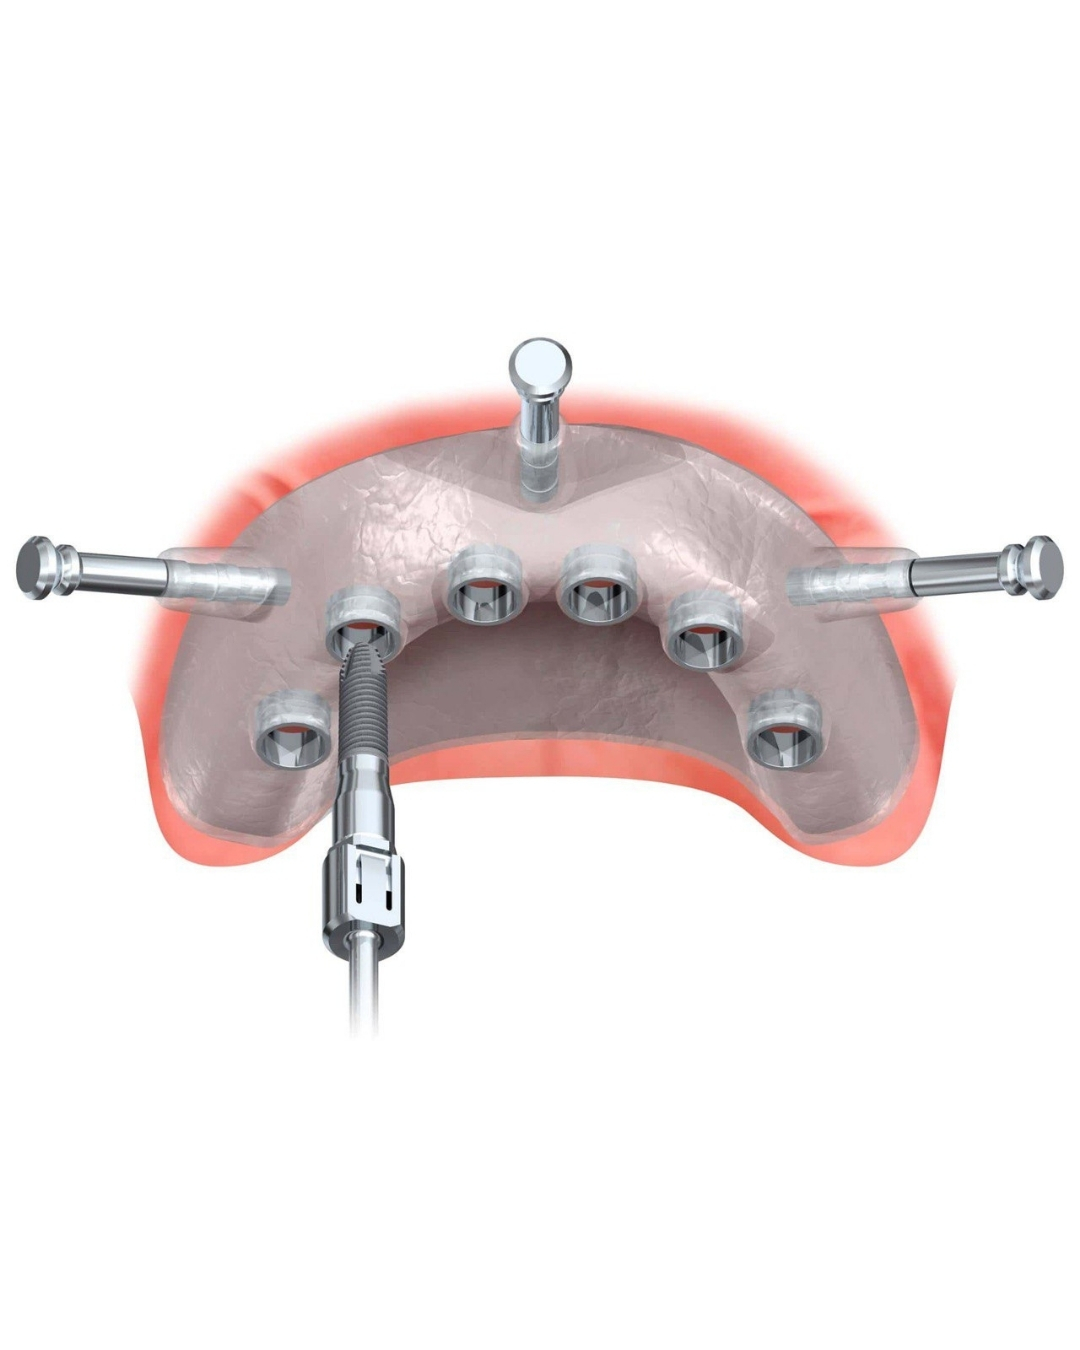

Navigačná implantológia - moderný prístup k presnej a predvídateľnej liečbe

Navigačná implantológia je inovatívna technológia umiestňovania zubných implantátov, založená na digitálnom plánovaní a použití navigačných šablón alebo dynamických systémov. Tento prístup zabezpečuje najpresnejšie umiestnenie implantátov v súlade s anatomickými vlastnosťami pacienta a plánovaným ortopedickým návrhom.

Podstatou metódy je vytvorenie detailného 3D modelu čeľuste, ktorý sa získa pomocou počítačovej tomografie. Na základe týchto údajov lekár vytvorí virtuálny chirurgický plán: určí optimálny počet, veľkosť, uhol sklonu a hĺbku umiestnenia implantátov. Tento plán sa potom použije na vytvorenie chirurgickej šablóny alebo na prácu s dynamickým navigačným systémom, ktorý riadi pohyb nástrojov v reálnom čase.

Výhody navigačnej implantológie:

- Vysoká presnosť: minimálna chyba pri umiestňovaní implantátov.

- Bezpečnosť: znižuje sa riziko poškodenia anatomických štruktúr - nervov, dutín atď.

- Minimálna trauma: často nie sú potrebné rezy a veľké objemy kostného štepenia.

- Predpokladaný výsledok: implantáty sa umiestňujú v súlade s budúcim ortopedickým návrhom, čo zlepšuje estetiku a funkciu.

- Komfort pacienta: skracuje sa čas operácie a pooperačná rehabilitácia.

Na čo sa používa navigačná implantológia?

Táto metóda je obzvlášť účinná v zložitých klinických situáciách – s nedostatkom kostného tkaniva, atypickou anatómiou, potrebou okamžitého zaťaženia alebo vysokými estetickými požiadavkami. Navigácia umožňuje dosiahnuť výsledky, ktoré boli predtým dostupné len najvyšším špecialistom s rozsiahlymi skúsenosťami.